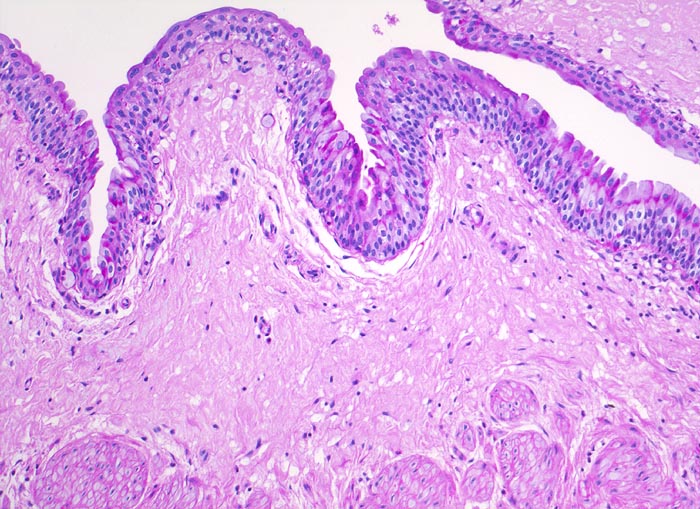

PathoPic ID 4201 - normaler Ureter

normaler Ureter

Normalbefund

Ureter

Niere, Harnwege

Die Zellen des Übergangsepithels enthalten wenig PAS positives (rotes) Glykogen.

Histologie

100